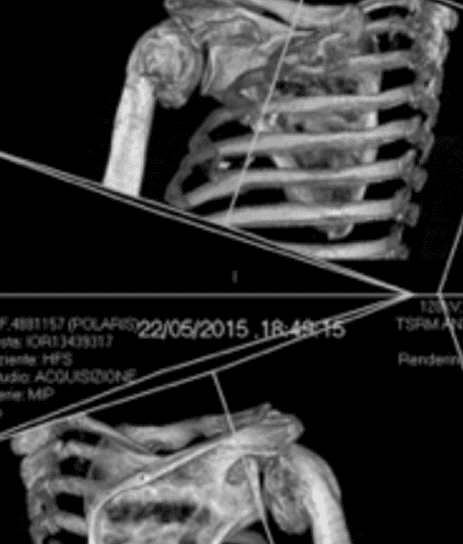

Patient Cases